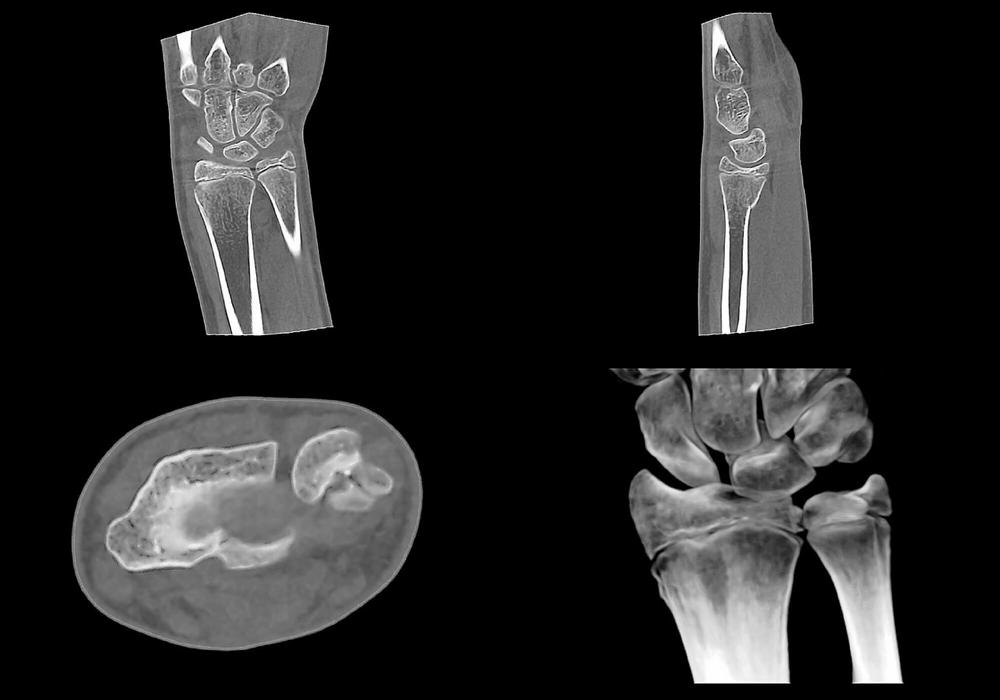

Das breite Anwendungsspektrum der digitalen Volumentomographie (DVT) in der O&U ergibt sich aus der hochauflösenden und strahlungsarmen Bildgebung sowie aus der einfachen Anwendung am Patienten. So hat sich die 3-D-Schnittbildgebung mit dem digitalen Volumentomographen SCS MedSeries® H22 auch im Bereich der Extremitätendiagnostik bei Kindern und Jugendlichen etabliert. Im Hinblick auf die Wahl eines geeigneten Diagnostikverfahrens […]